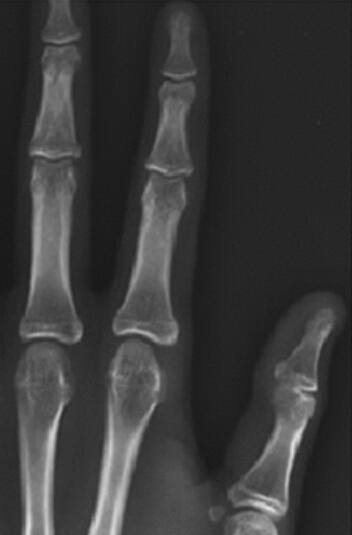

What is the diagnosis? What makes you think so?

Reflex sympathetic dystrophy

there is pretty severe demineralization and the joint spaces are good